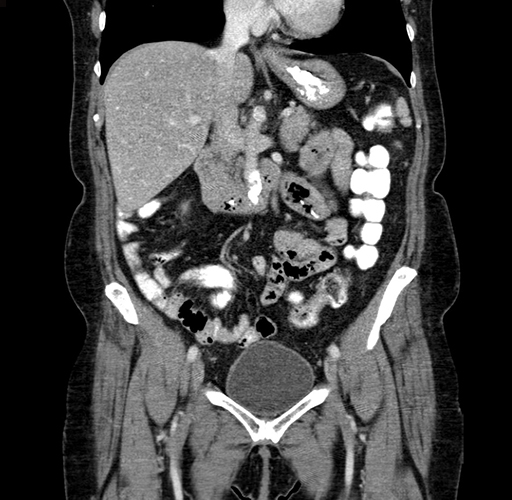

Pre-Chemo: Coronal Venous